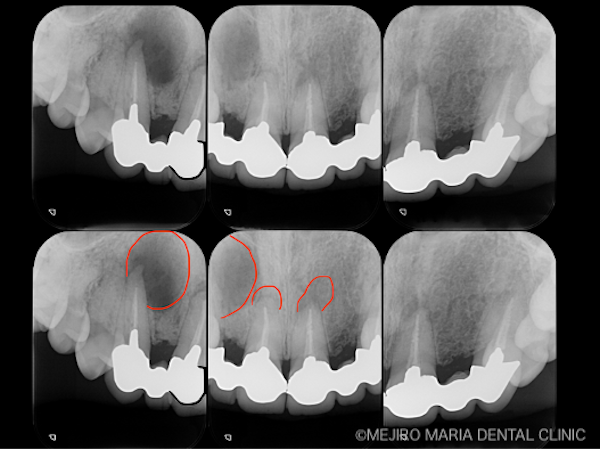

赤で囲んだ部位は透過像(根尖性歯周炎)

診査を行ったところ、上顎右側3番(犬歯)の根尖部付近に、根尖性歯周炎と見られる透過像が大きく広がっていました(写真 下段左)。また、上顎左右1番(中切歯)にも同様に病変が確認できました(写真 下段中)。

患者様は、日常生活では特に違和感を感じることはないそうですが、上顎右側3番根尖部を触診すると、明らかな違和感を訴えていました。